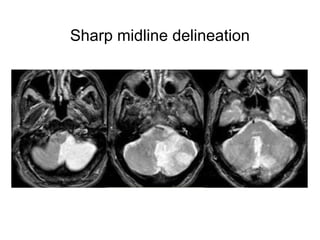

PICA Infarction

Sharp midline delineation

SCA territory